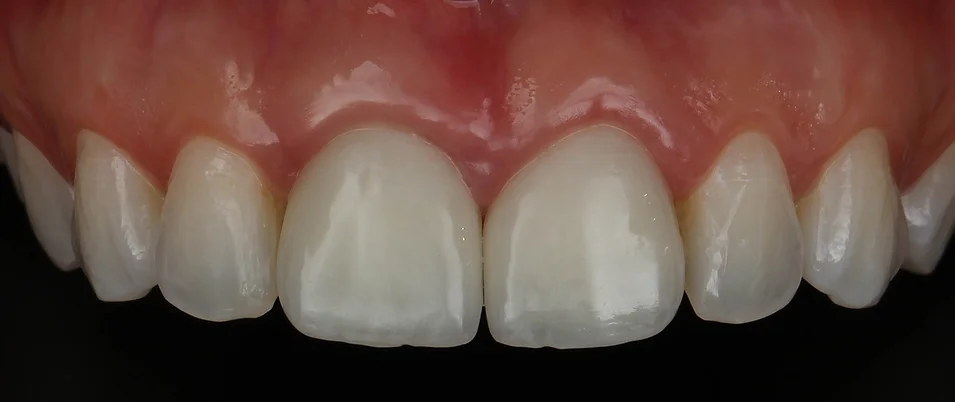

Estava diante de um grande desafio: devolver a arquitetura gengival alterada pelas facetas inadequadas já presentes tendo que realizar um implante dentário na região de incisivo central de uma paciente jovem, com sorriso gengival, filha de dentista e que só queria mudar esses dois dentes.

Realizamos então a exodontia do incisivo central superior direito, seguido de implante, enxerto 100% com biomaterial, provisório imediato e posterior troca da faceta do incisivo central superior esquerdo. A maior preocupação era utilizar uma técnica cirúrgica que mantivesse o alinhamento da gengiva com os dentes vizinhos e uma reabilitação protética que escondesse o implante e a faceta do dente vizinho no conjunto do sorriso.